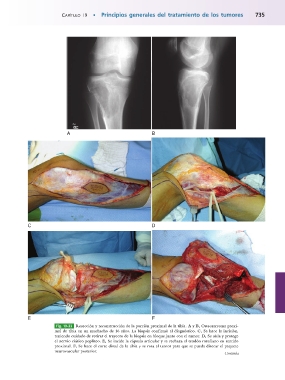

Fig. 19-33 Resección y reconstrucción de la porción proximal de la tibia. A y B, Osteosarcoma proxi-

mal de tibia en un muchacho de 16 años. La biopsia confirmó el diagnóstico. C, Se hace la incisión,

teniendo cuidado de retirar el trayecto de la biopsia en bloque junto con el tumor. D, Se aísla y protege

el nervio ciático poplíteo. E, Se incide la cápsula articular y se rechaza el tendón rotuliano en sentido

proximal. F, Se hace el corte distal de la tibia y se rota el tumor para que se pueda disecar el paquete

neurovascular posterior. Continúa